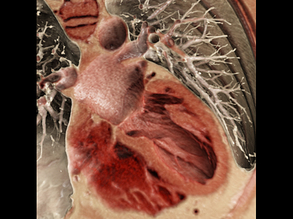

Follow the Heart